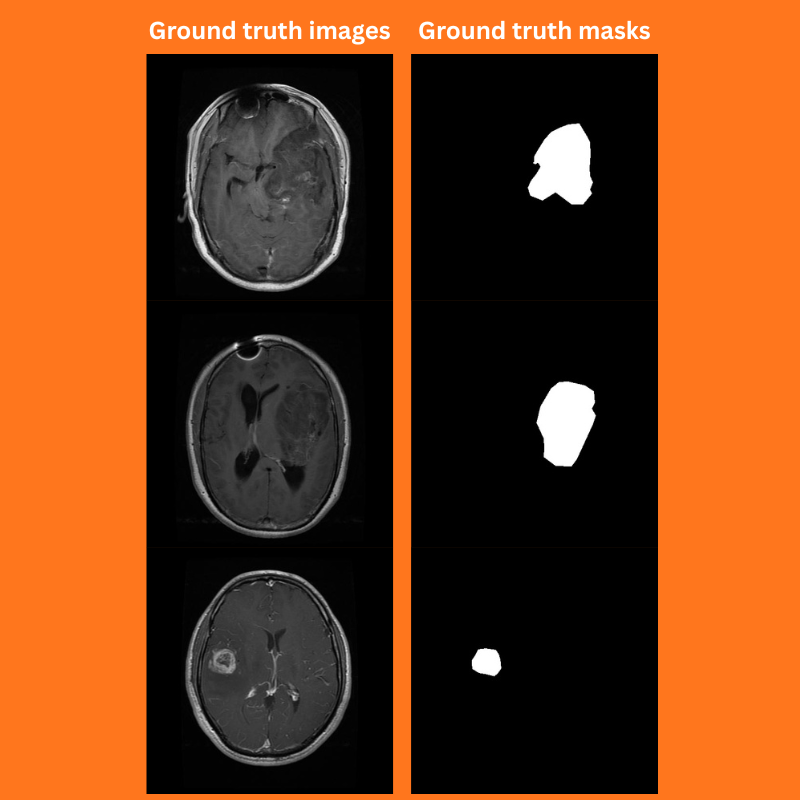

ALL_CLASSES: ['background', 'tumor'] LABEL_COLORS_LIST: [ [0, 0, 0], [255, 255, 255] , ] VIS_LABEL_MAP: [ [0, 0, 0], [0, 255, 0], ]

The LABEL_COLORS_LIST is used during the dataset preparation. The color values represent the palettes used for different objects. For background, it is black, and for the object, it is white. This should match the values used in the ground truth masks.

The VIS_LABEL_MAP is used for visualization during inference. Instead of white, we use green for visualization.